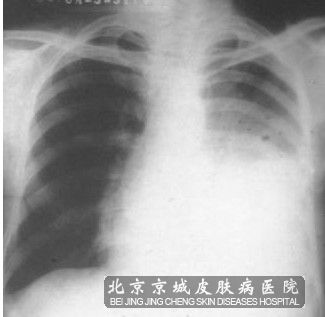

在肺部鳞状*癌的发病早期,肺癌的病患处通常较低症状的症状表现,而当有症状出现时,则往往表明肺癌已经处在进展当中了。肺部鳞状*癌的表现主要与肿瘤的部位、大小、分期、是否发生转移等因素有关。

常见的症状主要包括慢性咳嗽、咯血、胸闷、气急、发热、胸痛、声音嘶哑、食欲及体重逐渐下降等。这些症状也可由胸部的其它疾病引起,所以一旦有症状出现,应该尽快到医院检查以明确病因,避免延误病情,给自身带来不必要的伤害。